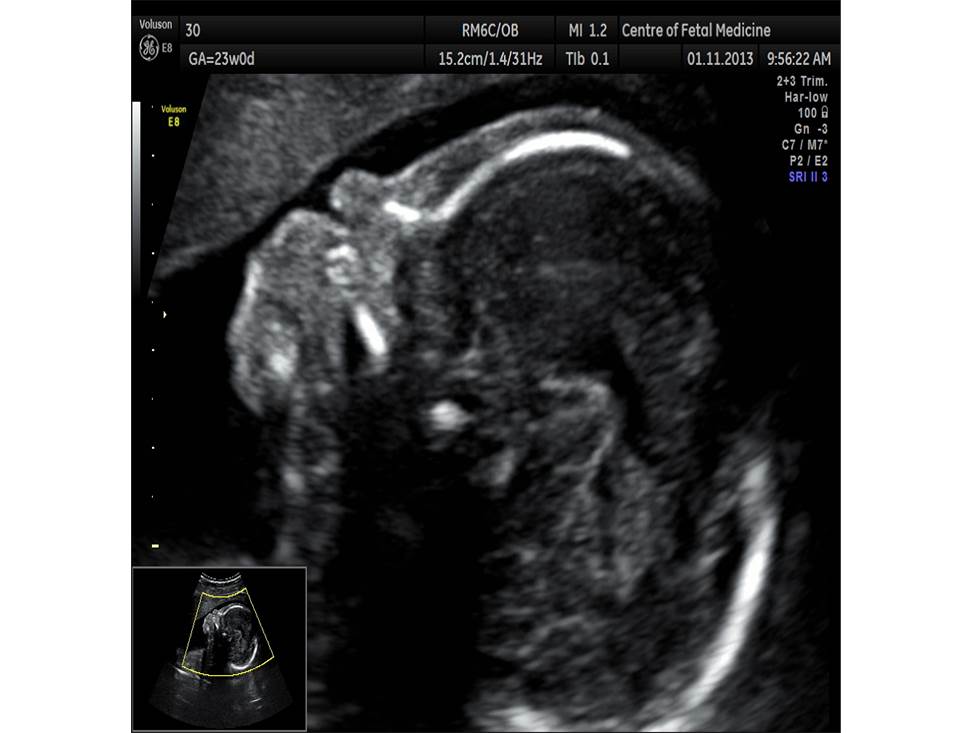

Вопрос 3

- Проанализируйте изображения плода в 19 недель, есть ли у него какие-либо маркеры хромосомной патологии?

- Необходимо ли рекомендовать инвазивную диагностику? Пациентке 28 лет, в 1 триместре комбинированный риск по трисомии 21 — 1:1220

Данные 1 скрининга